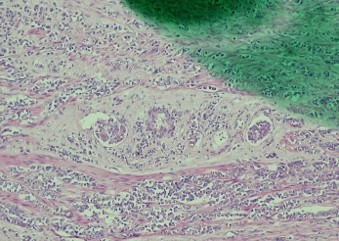

Pathology of the right hemicolectomy specimen was “involvement by metastatic carcinoma, immunoprofile compatible with breast primary”. The cytokeratin profile was CK7+, GATA3+ and MOC-31+, and negative for CK20 and CDX-2. There was very focal positivity for E-cadherin, while p120 catenin mostly showed cytoplasmic staining in the tumour cells. Microscopic examination suggested that the tumour invaded from mucosal side of the intestinal towards the serosa; the proximal and distal resection margins were clear. The morphology and immunoprofile point towards a metastatic carcinoma of breast.